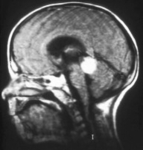

Aspect of trilateral retinoblastoma (MRI)

Aerts I, et al. Orphanet J Rare Dis 2006 Aug 25; 1: 31; licensed under CC BY 2.0